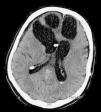

Spontaneous pneumocephalus following cerebrospinal fluid shunt is a rare complication. In most cases, the air enters in the intracranial cavity via a skull base defect. We report 2 cases of delayed tension pneumocephalus, secondary to ventriculoperitoneal shunt, and review the etiopathogenesis, prevention and treatment of this condition.